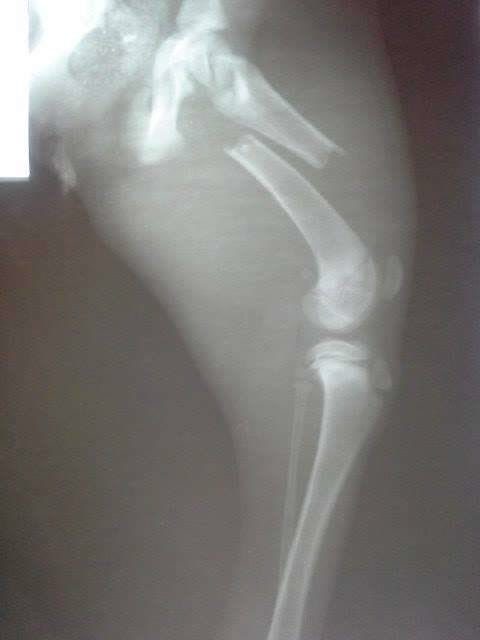

Hit by a car

He was living his life in a market, where people threw him a bit of bread at times. At night, he took shelter under the market stands, or under a car parked in the market place. Yet, everything turned into a nightmare, when a car backed up and the poor dog couldn’t get out of the way. He was left there unable to move, while the heartless person who hit him abandoned him and went on with his life. A desperate call from a lady who worked at the market drew our attention, and we could not ignore the situation, although we are swamped with animals and problems of all kinds. The little dog’s first surgery was successful, and now he is at the clinic, where he will have to undergo more surgery. We hope that in the end he will walk again.